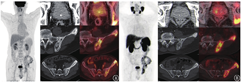

18F-FDG与68Ga-PSMA-11 PET/CT显像(图1)可见前列腺增大,最大横截面5.7 cm×4.4 cm,18F-FDG与68Ga-PSMA-11摄取不均匀轻度增高,其中右叶腺体见小片状68Ga-PSMA-11摄取增高区,中央腺体见钙化灶;另见左侧骨盆弥漫性成骨性病变,密度不均,18F-FDG与68Ga-PSMA-11均摄取增高,68Ga-PSMA-11摄取增高更显著。18F-FDG对前列腺癌的诊断效果欠佳,灵敏度仅有30%~50%[1],而68Ga-PSMA则大大提高了PET技术在前列腺癌中的诊断灵敏度[2]。本例患者有明确的骨骼病变,68Ga-PSMA-11摄取呈阳性,前列腺也可见1处68Ga-PSMA-11摄取轻度增高病灶,但此处病灶与MR提示的病变部位并不一致,另外前列腺穿刺活检也未提示肿瘤性病变。本例是否为前列腺癌伴骨转移呢?是否要建议患者再次行穿刺活检或者行骨盆病变活检吗?

再来看前列腺的病灶。68Ga-PSMA-11 PET/CT见前列腺右叶有小片摄取轻度增高区,但根据MR的提示,该处摄取增高区在MR上并未见异常信号,无解剖影像上支持的证据。PSMA是具有750个氨基酸的跨膜糖蛋白,在前列腺癌细胞中表达程度明显上调。但PSMA表达也并非绝对的前列腺癌特异性,多种非前列腺组织和病变也可见PSMA摄取,如副唾液腺、腹腔神经节、胆囊、Paget′s骨病、反应性淋巴结、肺癌、肾细胞癌、神经内分泌肿瘤、骨髓瘤、纤维发育不良、血管瘤、骨折等,可能导致PSMA PET假阳性结果[3]。

Paget′s骨病是一种成人的慢性骨骼疾病,55岁以上人群多见,西欧、北美等地区的人群发病率高于亚洲人群。Paget′s骨病的特征为局部骨转化增加,正常的基质被软化和增大的骨性结构所取代,常见于骨盆(70.0%)、股骨(55%)、腰椎(53%)、颅骨(42%)和胫骨(32%)[8]。Paget′s骨病患者可无症状,并在影像学检查中偶然发现,部分患者可有骨痛或伴局部皮温增高及压痛。患者的血清碱性磷酸酶通常增高,且由于破骨细胞异常、骨强度降低,可以发生骨折、畸形[8]。如前所述,PSMA在Paget′s骨病中可有阳性摄取,可能与骨重塑和新生血管增加有关[9],所以本例68Ga-PSMA-11 PET/CT的表现也支持Paget′s骨病的诊断。患者2016年11月行左侧髂骨活检,病理未见肿瘤,血清碱性磷酸酶222(正常参考值范围:45~125) U/L,骨盆正位X线片提示左侧髂骨大片骨质密度增高影(图2),符合Paget′s骨病诊断。患者后于本院门诊规律随诊至2023年6月,临床诊断为前列腺增生。